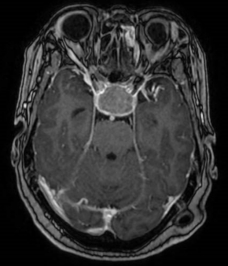

听神经瘤术前核磁 术后CT

第一位患者因听神经瘤导致部分听力丧失,肿瘤与负责面部表情的面神经和负责咀嚼功能及面部感觉的三叉神经粘连紧密,手术如同在“生命禁区”里拆除一枚紧贴着关键“线路”的高危炸弹,稍有不慎便会损伤重要血管和神经,风险极高。

在术中神经电生理监测的精准“导航”下,李智教授携手市第一人民医院神经外科团队,以毫米级精度将肿瘤和面听神经、脑干组织、血管等进行“抽丝剥茧”式的分离。经过6小时的精细操作,最终肿瘤被完整切除,患者的面神经与三叉神经功能也得以完好保留,最大限度地避免了术后面瘫、面部麻木等严重并发症,保障了患者术后的生活质量。